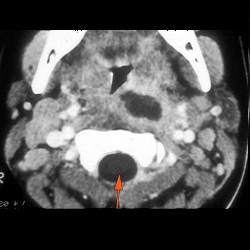

Suppurative Retropharyngeal Adenitis 2

Cases with suspected soft tissue infection.